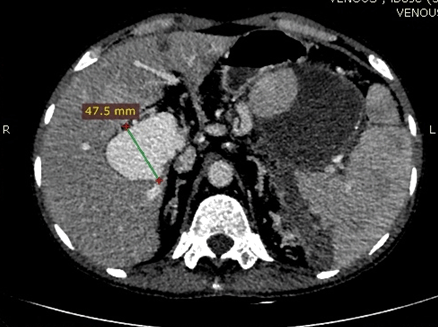

A 56-year-old male with no known medical comorbidity presented with complaints of vague upper abdominal discomfort associated with nonspecific left sided headache for one month and fever on and off for 15 days. On examination, he was conscious, comfortable and cooperative with a blood pressure of 130/70 mmHg and a pulse rate of 84/min. On abdominal examination, there was fullness in the epigastrium with tip of the spleen palpable below the left costal margin. Computed tomography angiography of the abdomen revealed a large heterogeneous mass near the splenic hilum measuring around 9×8.3 cm in the axial plane and approximately 8.6 cm in its craniocaudal extent in relation to the tail of pancreas bulging into the lesser sac and abutting the greater curvature of stomach with faint contrast uptake along the periphery with another large hyperdense mass within, consistent with a large splenic artery aneurysm containing a thrombus (Figure 1). On the arterial phase scan, there was minimal enhancement within this lesion. The spleen was enlarged with an infarct in its lower pole. The liver was grossly normal with no nodularity. There was an aneurysmal dilatation of the portal vein at the porta hepatis, measuring 47.7 mm in the largest diameter (Figure 2).

Figure 2: Computed tomography angiography (coronal section) image showing minimal enhancement of the splenic artery aneurysm on the arterial phase with minimal portal venous phase enhancement; Portal vein aneurysm enhancing well on the venous phase.

Figure 1: Computed tomography angiography image showing the splenic artery aneurysm with an organized clot within and the portal vein aneurysm (47.7 mm) on the transverse section.